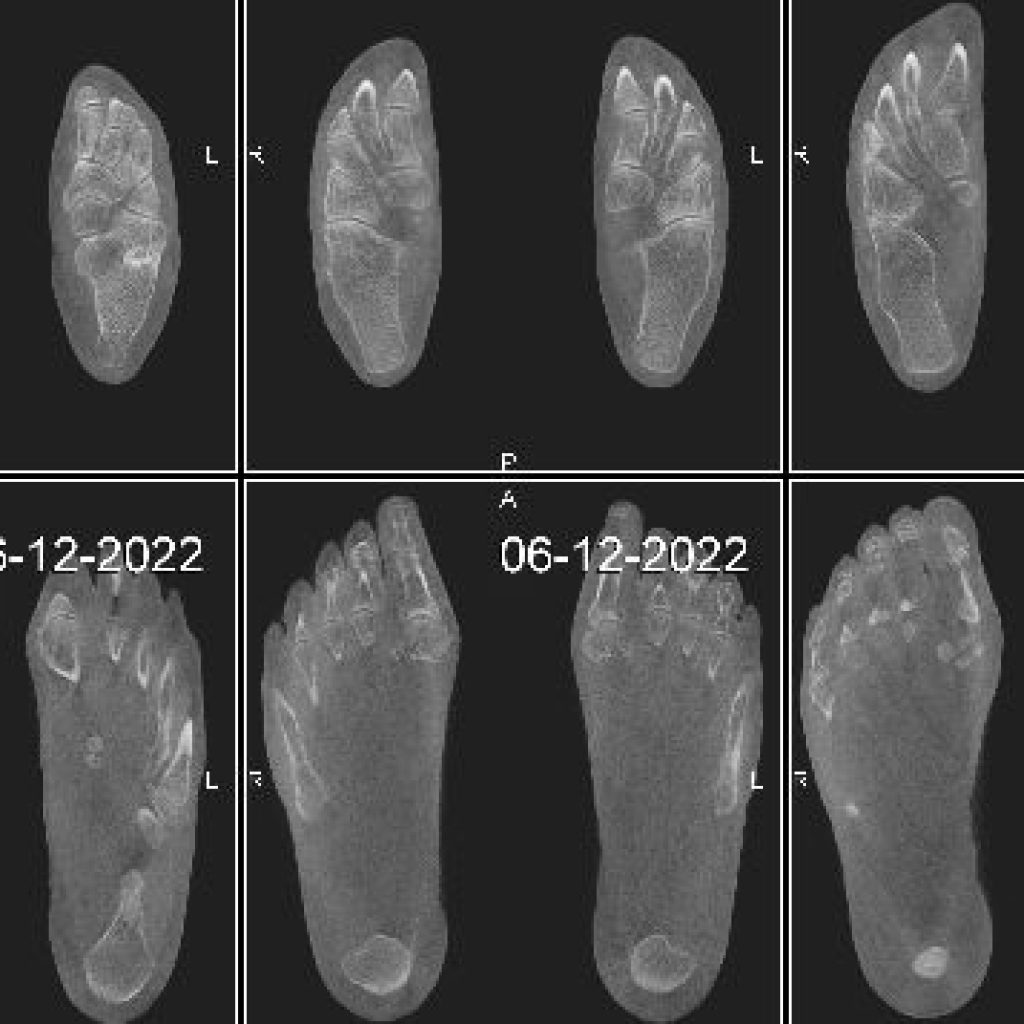

Il s’agit d’un appareil type cone beam permettant d’étudier en position débout, comme un scanner, les pieds, les chevilles et les genoux avec une très faible irradiation du patient comparé à un scanner conventionnel.

Il suffit de moins d’une minute pour obtenir une acquisition volumique 3D des pieds et des chevilles.